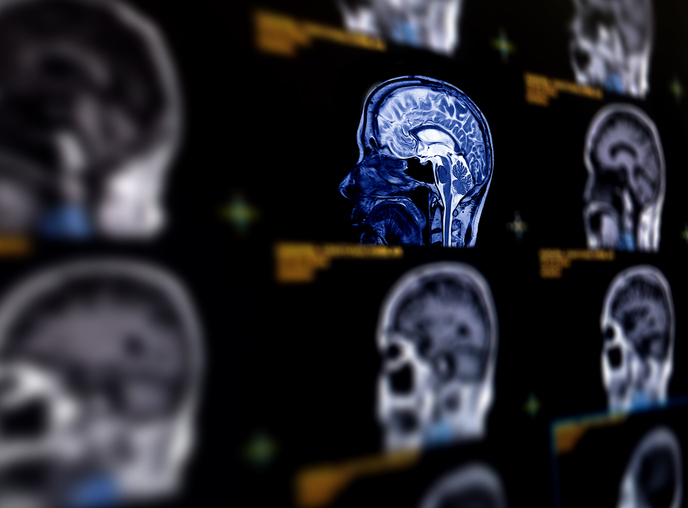

How doctors diagnose a brain aneurysm after an accident

Brain aneurysms are often discovered during scans performed for other reasons. After a car accident, doctors may order imaging to evaluate for head trauma, concussion, or internal bleeding. In the process, they may find an undiagnosed aneurysm.

If symptoms point to a possible rupture or leak, more advanced imaging is usually ordered right away. The goal is to identify the source of the problem as quickly as possible so treatment can begin.